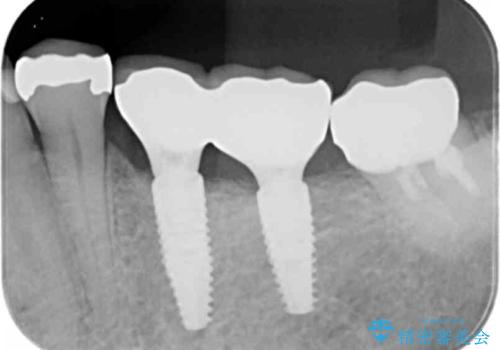

- 銀歯を装着してから時間が経っているので一度外して審美的な修復治療を受けたい、と希望され来院されました。

銀歯周囲の天然歯を削らないよう、拡大鏡下で丁寧に銀歯を除去したのちに審美性・精密性に優れるセラミックインレーを用いた修復治療を行っていきます。